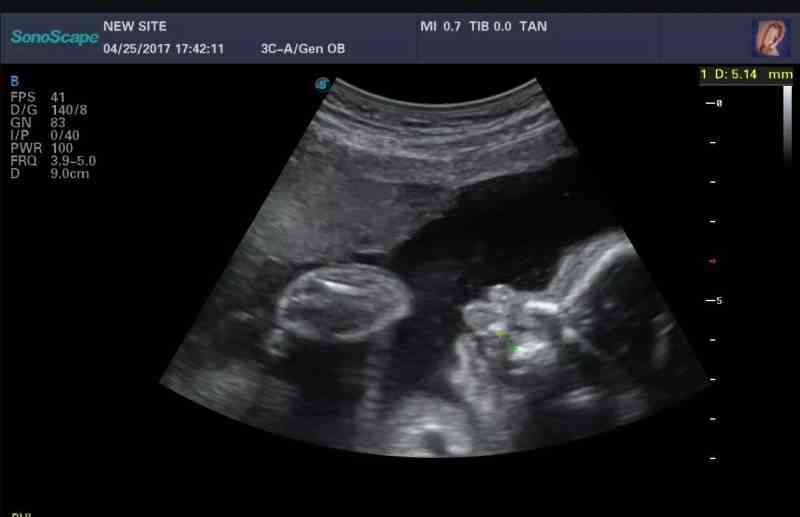

畸形胎儿,无脑儿引产三个多月后,要备孕需要做哪些检查?

4月份怀孕后,孕16周确认无脑儿,吉大二院开具产前诊断,回本地做引产。夫妻双方在吉大二院做的染色体检查,无异常,胎儿引产后未做检查。现在引产近三个月,想问一下大家,有过一次生化,一次无脑儿,如果备孕,还需要做哪些检查,叶酸应该怎么吃?